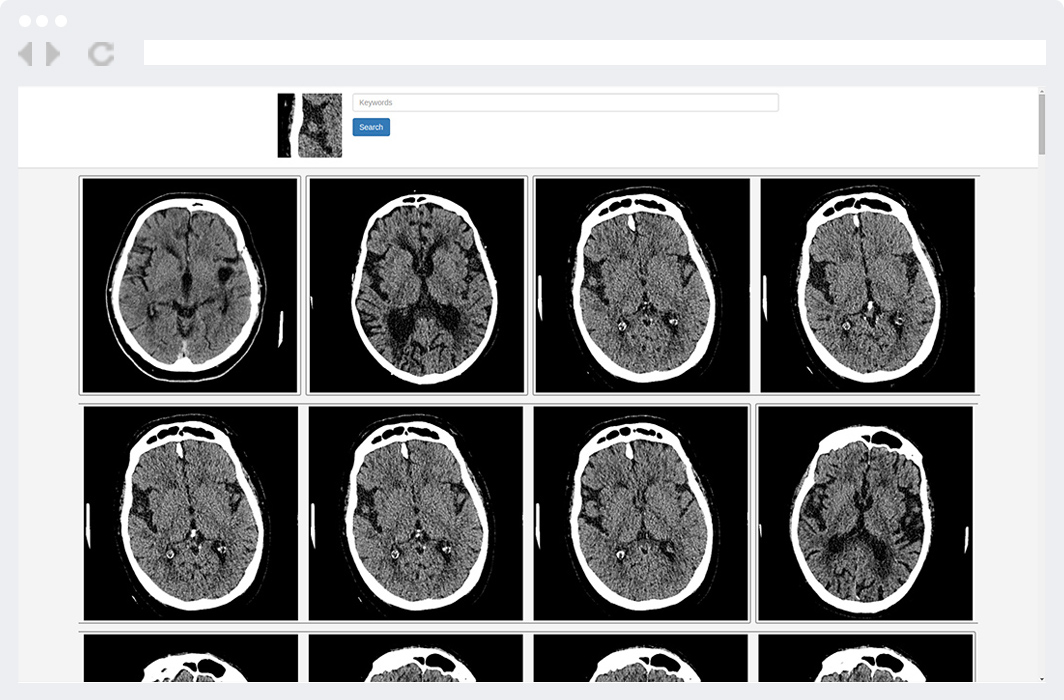

With list of results radiologist can compare images, read anonymized reports and/or view whole studies. After that radiologist makes a report or performs another search.